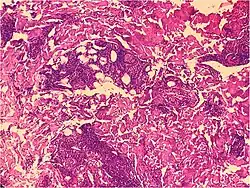

| Kaposi’s sarcoma in patch stage | The patch stage typically shows irregular proliferation of jagged vascular channels in the dermis below an integral epidermis. The so-called promontory sign is sometimes found in patch stage lesions and denotes vascular spaces surrounding pre-existing blood (see image).[23] vessels |   |   |